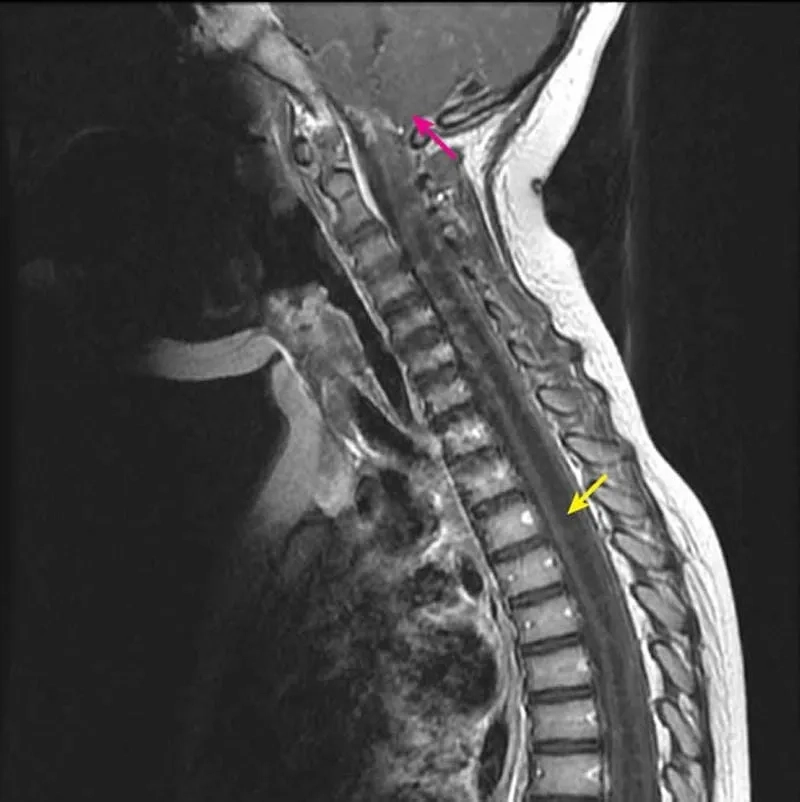

• Regular monitoring with MRI scans is essential to track the size and progression of the syrinx and determine the best timing for surgical intervention.

A before-and-after MRI following syringomyelia treatment